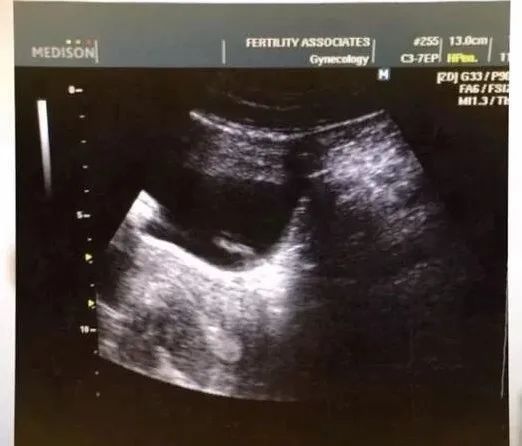

之后便是一波三折的受孕过程,第一次胚胎植入失败了,没有怀孕。第二次胚胎植入成功怀孕,但5周之后流产了。Lacey承受着流产的痛苦,同时还对好友心怀愧疚,为什么就流产了呢?

所以第三次胚胎移植的时候,Lacey心情非常忐忑,这也是最后一轮的尝试。

当不久后,她在超声波检查里听到胎儿的心跳声时,忍不住哭了出来,大家都相拥而泣。